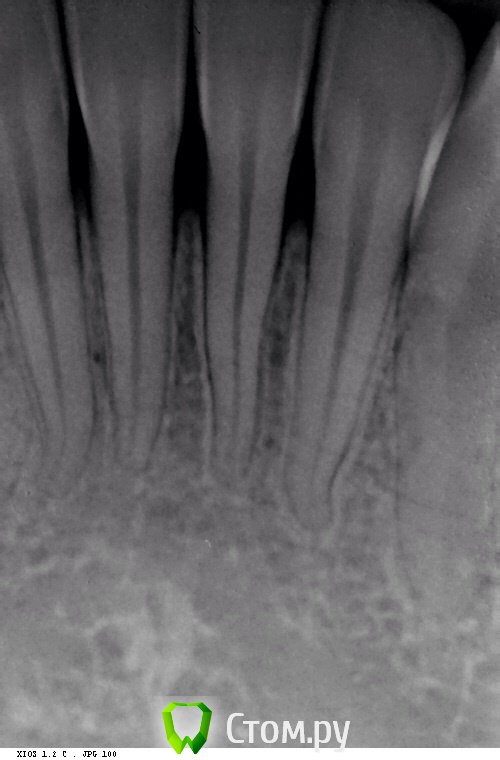

Naga Siren Опубликовано 20 октября, 2014 Автор Поделиться Опубликовано 20 октября, 2014 (изменено) Хорошо, спасибо, я тогда в лс напишу.Прилагаю еще фото Изменено 20 октября, 2014 пользователем Naga Siren Ссылка на комментарий